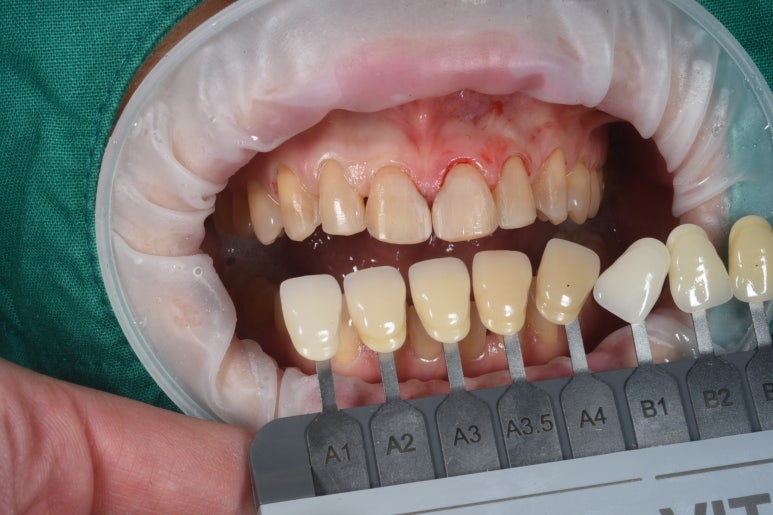

최소한의 치아 다듬기가 필요합니다.

압구정 치과 라미네이트를 붙이기 전 치아를 다듬은 모습입니다.

이게 정말 끝입니다.

어쩌면, 치아가 더 예뻐졌다고 생각하실지도 모르겠습니다. (?!)

수직, 수평 모양을 맞추고 날카로운 부위를 둥글리는 과정 정도로 이해해주시면 됩니다.

또한 표면을 매끈하게 만들어 제작된 레브네이트가 치아에 딱 잘 적합되게 하는 과정이지요.

스크롤을 위아래로 오르락 내리락 하시면서 확인해보세요!

기술의 발달로 라미네이트는 더 강해지고 더 얇아져, 치아를 폴리싱 하는 정도만 손보아도 라미네이트를 제작할 수 있게 되었습니다.!!